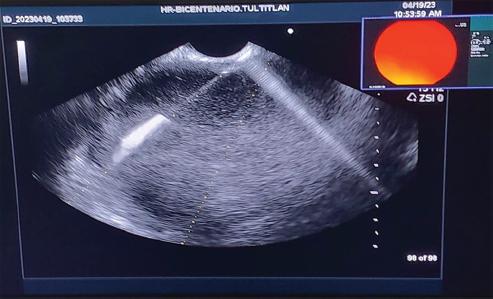

En las figuras 2-4 se ejemplifica el procedimiento que se realizó para obtener el material de la NQP, con descripción de cada una de ellas.